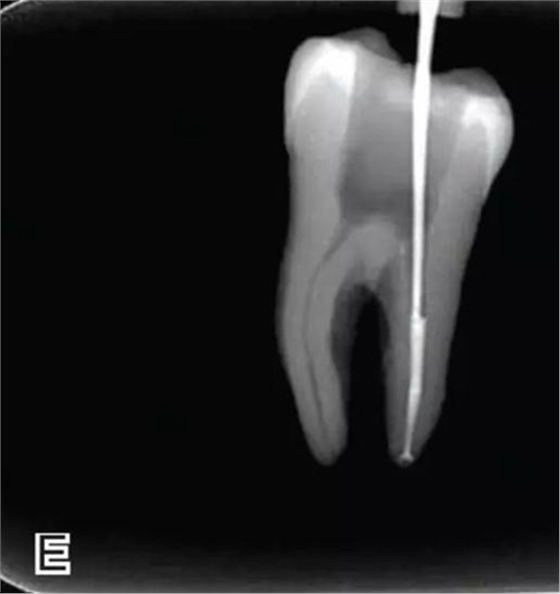

3、試尖

選擇非標(biāo)準(zhǔn)牙膠尖(如0.04、0.06 錐度牙膠尖)作為主尖,型號(hào)一般與根管預(yù)備最大號(hào)的器械型號(hào)一致,能到達(dá)距根尖0.5~1 mm 處,主尖尖段與根管壁緊密接觸。拍試尖X 線片進(jìn)行確認(rèn)(圖3)。

圖3 試尖,A.試主尖 B.拍試尖X片